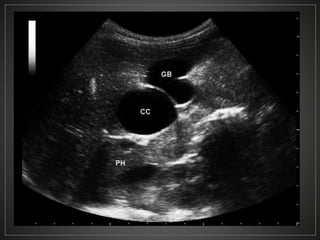

• #38 USG en escala de grises se observa en coledoco una imagen de morfologia redondeada, de bordes bien definidos, anecoica, sin septos ni ecos en su interior (CC) , localizada entre la cabeza pancreática (HP) y la vesícula biliar (GB), en relación a quiste del coledoco.